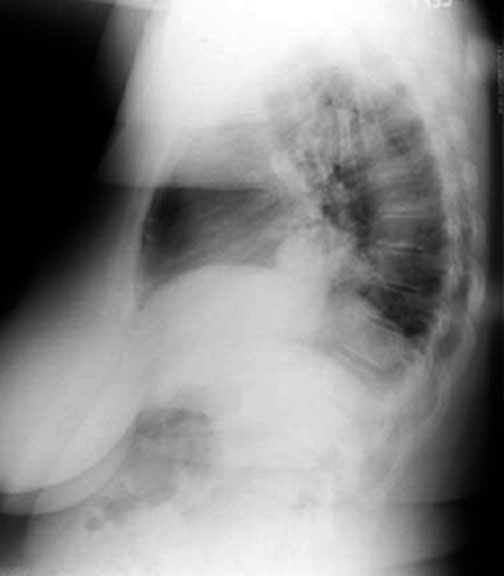

Eventration / Localized

• Herniation of Liver